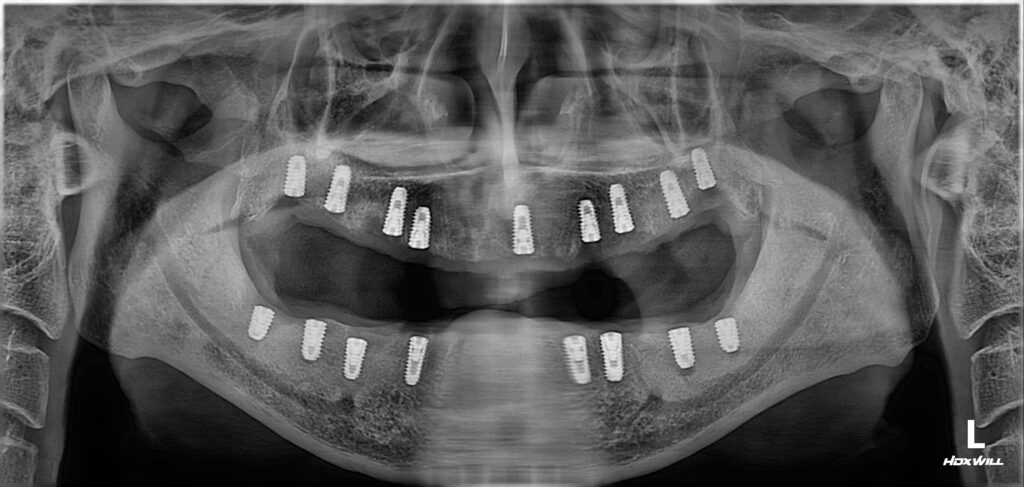

네비게이션 시스템을 활용한 전체 임플란트 수술

네비게이션 시스템을 활용하여 전체 임플란트 수술을 했습니다.

하루에 위아래 다하기엔 환자분이 너무 힘드실 거고 마취약도 많이 써야 하고, 출혈도 많이 될 거라 이틀에 걸쳐서 위아래 임플란트 수술했습니다.

염증으로 뼈가 많이 손상되어 있긴 했지만 뼈의 폭(너비)이 충분해서 뼈이식은 따로 할 필요가 없었습니다. 상악동 거상술 역시 필요치 않았습니다.

위와 같이 임플란트 수술을 마쳤습니다. 보기에 매우 좋죠?

보기에 좋은 떡이 맛도 좋듯이 보기에 좋은 임플란트가 기능도 좋고 튼튼합니다.^^